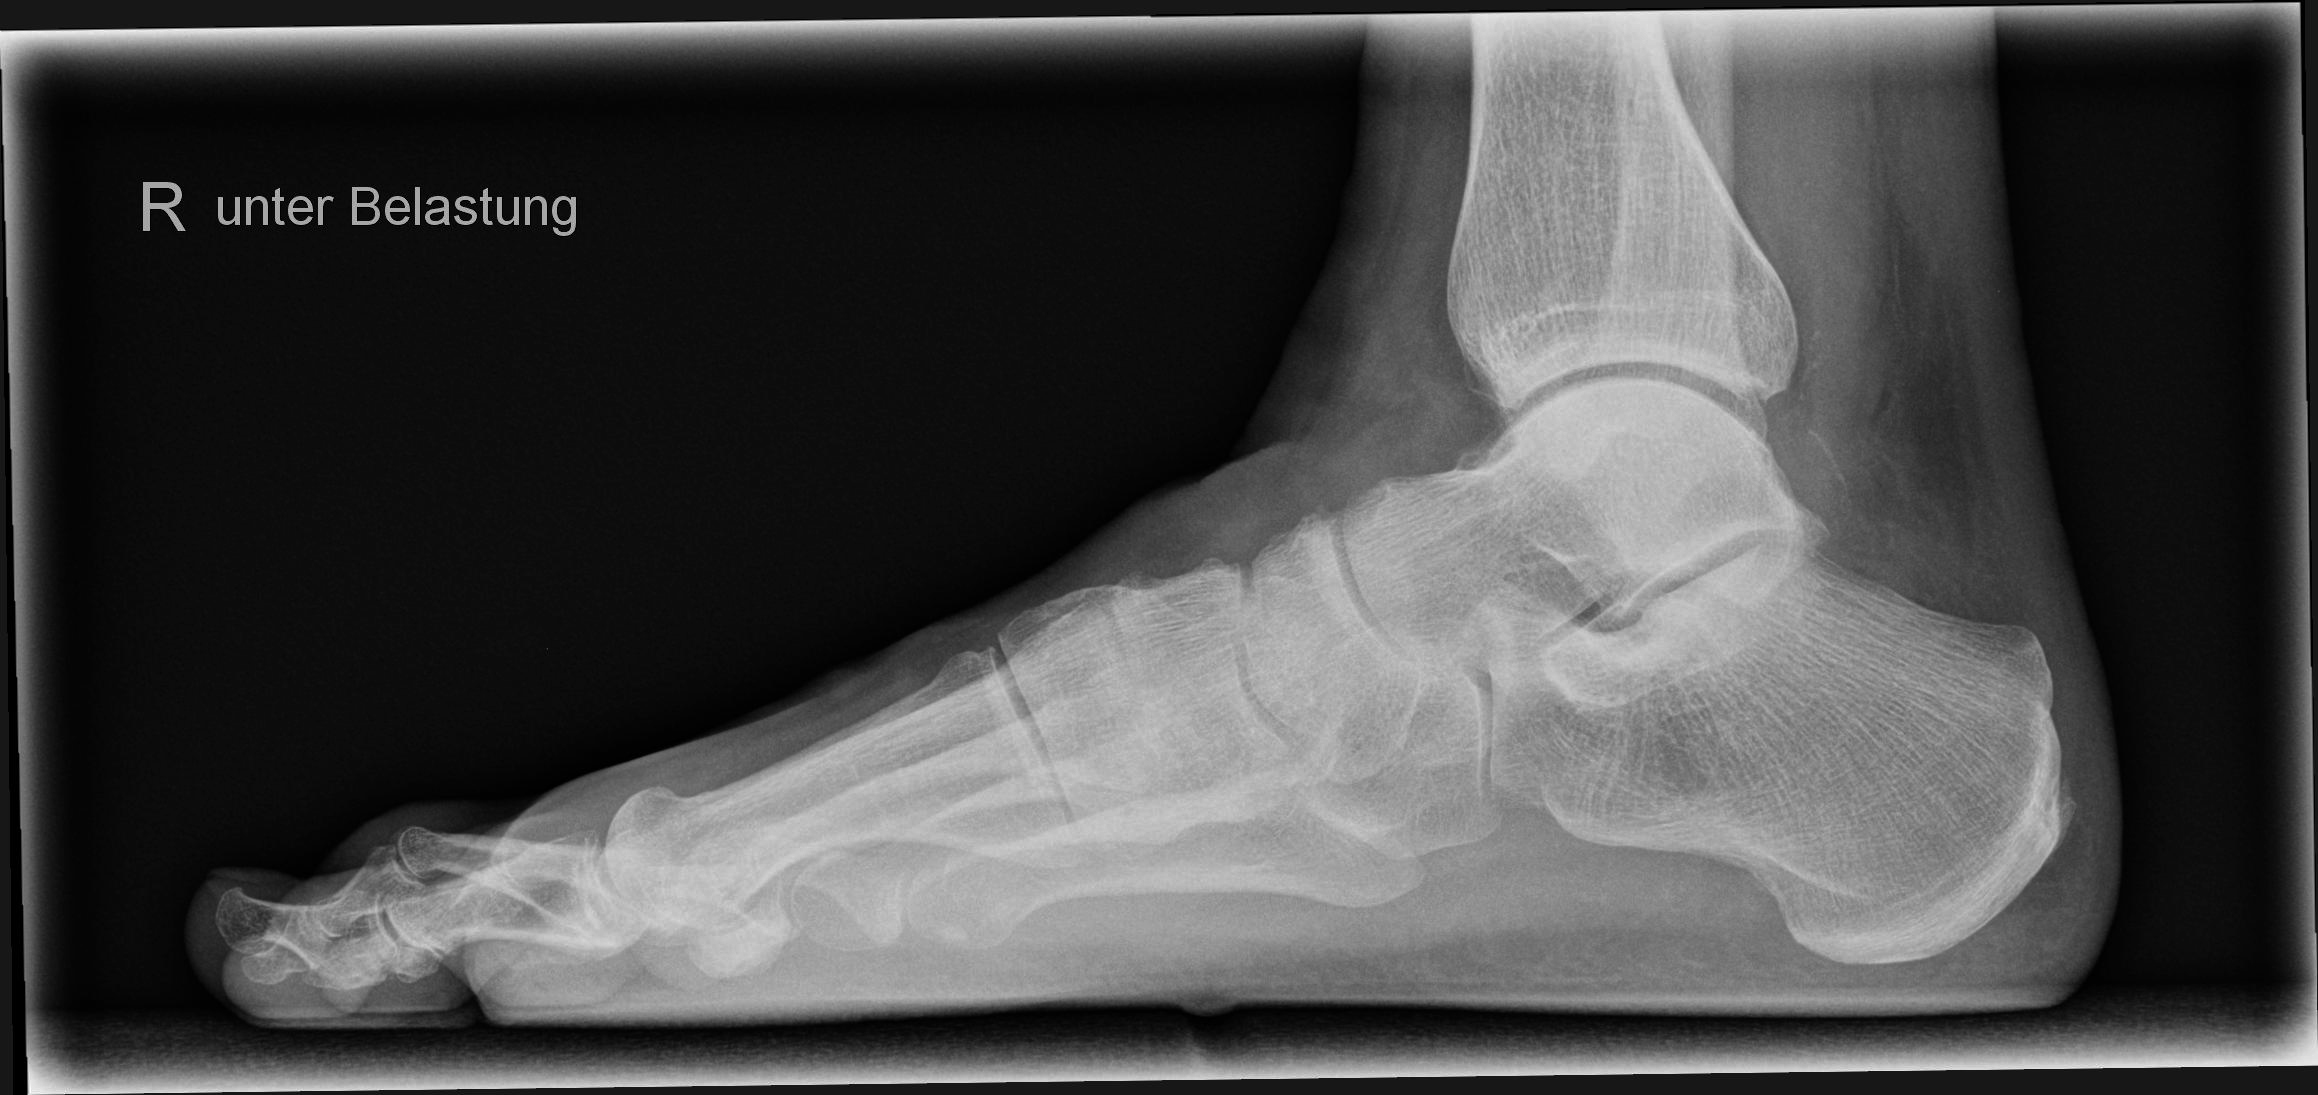

Fuß seitlich unter Belastung

Indikation

Zur Begutachtung eines Senk- und Plattfußes oder aber zur Beurteilung der Fußachse und des Halux.

Lagerung

stehend mit Außenseite zum Bildempfänger auf einem Sockel

zweiten Fuß nach hinten versetzen um das Gleichgewicht zu halten

untersuchenden Fuß voll belasten

zum Halt sollte sich der Patient auch irgendwo am Stativ festhalten

Zentralstrahl

senkrecht auf Objektmitte

Einblendung

gesamter Fuß einschließlich Ferse

Anmerkung

Sollte der Patient nicht auf einem Sockel stehen, wird die Fußsohle abgeschnitten. Deshalb der Detektor zwischen Stativ und Sockel stellen

Qualitätskriterien

Seitliche Aufnahme des ganzen Fußes. Die Mittelfußknochen und Phalangen überlagern sich. Oberes und unteres Sprunggelenk sind gut einsehbar. Überlagerungsfreie Darstellung des Fersenbeins.